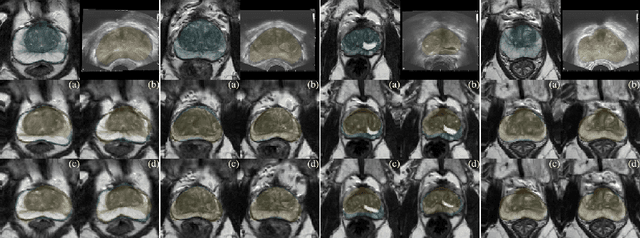

Abstract:Background and Objective: Accurate and reliable segmentation of the prostate gland in MR images can support the clinical assessment of prostate cancer, as well as the planning and monitoring of focal and loco-regional therapeutic interventions. Despite the availability of multi-planar MR scans due to standardized protocols, the majority of segmentation approaches presented in the literature consider the axial scans only. Methods: We propose an anisotropic 3D multi-stream CNN architecture, which processes additional scan directions to produce a higher-resolution isotropic prostate segmentation. We investigate two variants of our architecture, which work on two (dual-plane) and three (triple-plane) image orientations, respectively. We compare them with the standard baseline (single-plane) used in literature, i.e., plain axial segmentation. To realize a fair comparison, we employ a hyperparameter optimization strategy to select optimal configurations for the individual approaches. Results: Training and evaluation on two datasets spanning multiple sites obtain statistical significant improvement over the plain axial segmentation ($p<0.05$ on the Dice similarity coefficient). The improvement can be observed especially at the base ($0.898$ single-plane vs. $0.906$ triple-plane) and apex ($0.888$ single-plane vs. $0.901$ dual-plane). Conclusion: This study indicates that models employing two or three scan directions are superior to plain axial segmentation. The knowledge of precise boundaries of the prostate is crucial for the conservation of risk structures. Thus, the proposed models have the potential to improve the outcome of prostate cancer diagnosis and therapies.